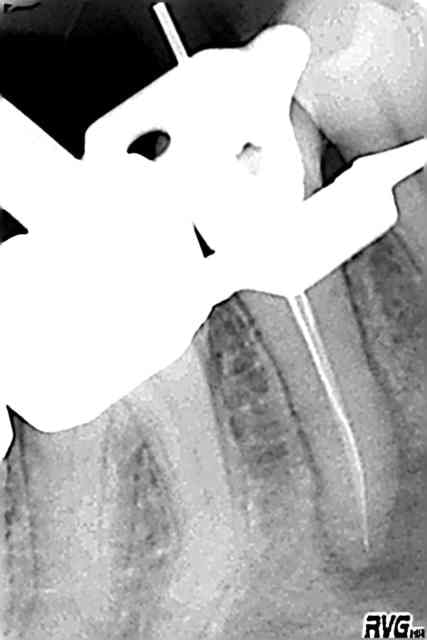

patiente en urgence la semaine dernière

douleurs sur 45 traitée en 2004 (à peu près correctement je trouvais mais sans digue et probablement pas assez hypoclorisée)

ttt repris ce jour(inutile de s'extasier ou critiquer,c'est une reprise lambda)

45 broche en place jdrvuc - Eugenol